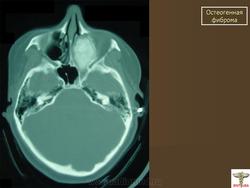

Фиброма остеогенная.

Фиброма остеогенная